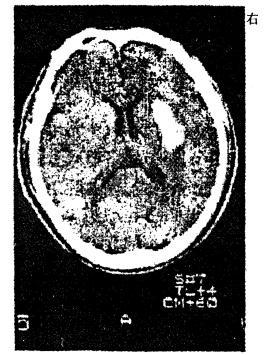

问题 男性,56岁。高血压患者。旅游登山中突然左侧 肢体发麻、乏力。急送医院,摄头颅CT片如图 病损部位在 A.左侧大脑皮质 B.右侧大脑皮质 C.左侧基底节区 D.右侧基底节区 E.小脑

答案 D